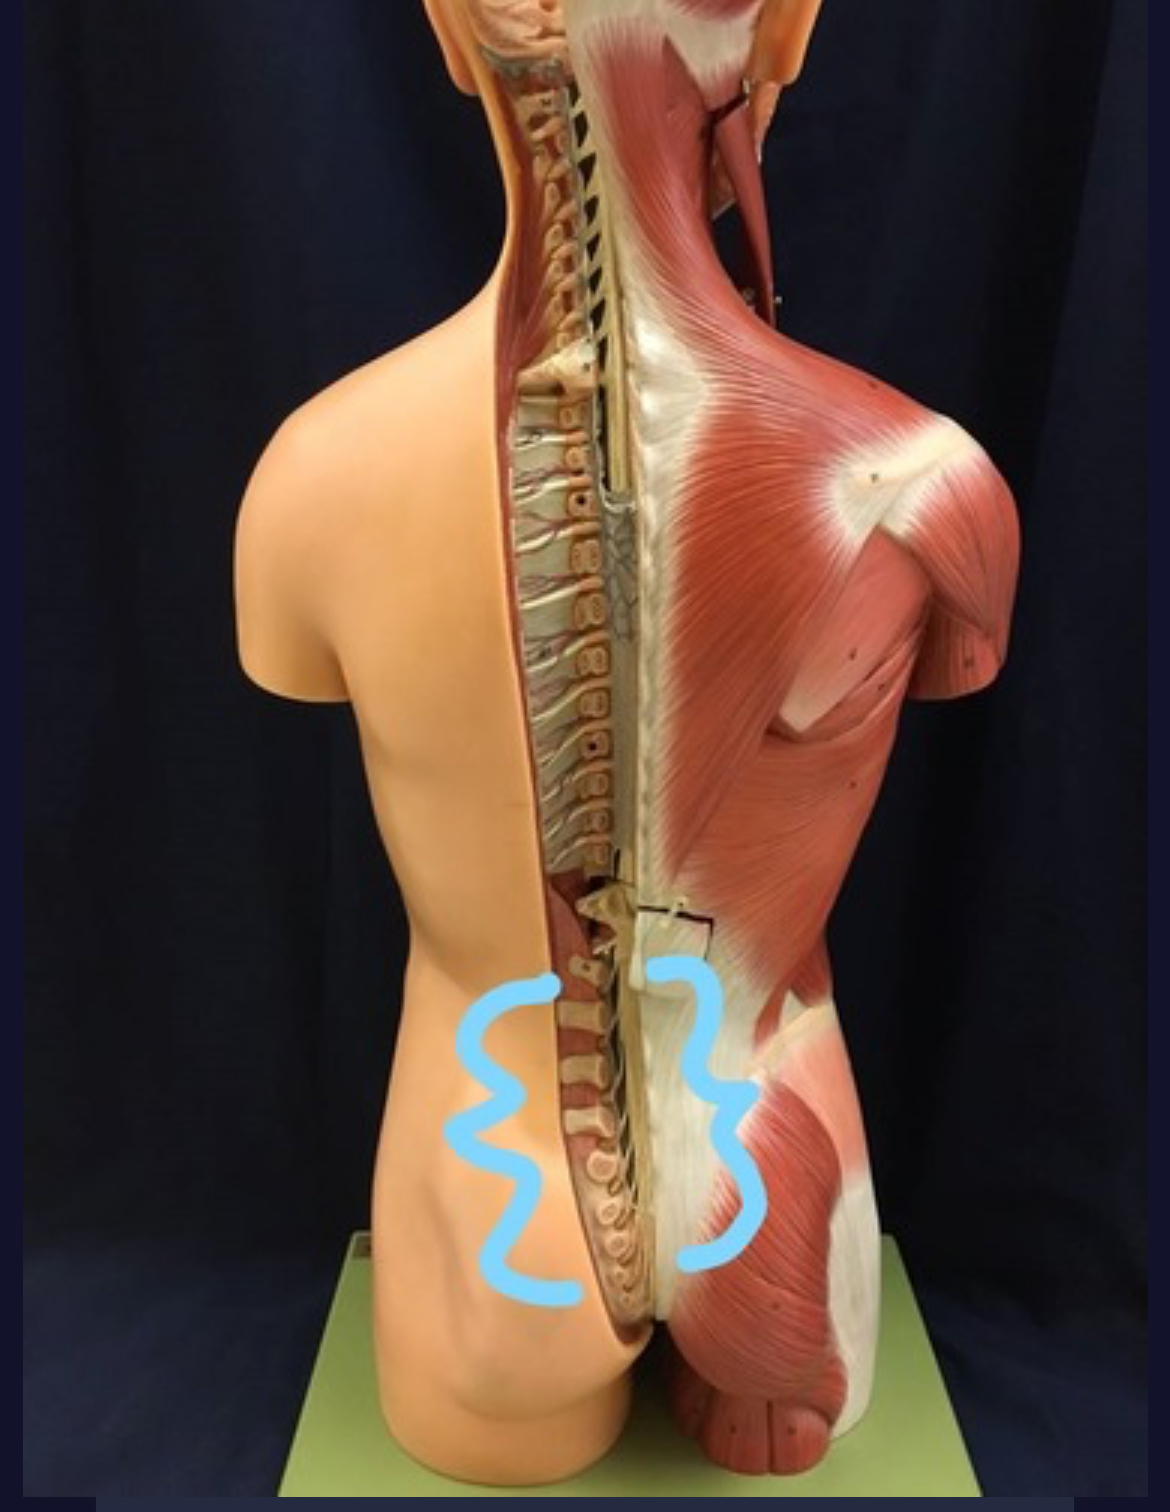

Spinal cord

Cauda equina

Dorsal root ganglion

Dorsal root

Ventral root

Spinal nerve

Dorsal Ramus

Ventral ramus